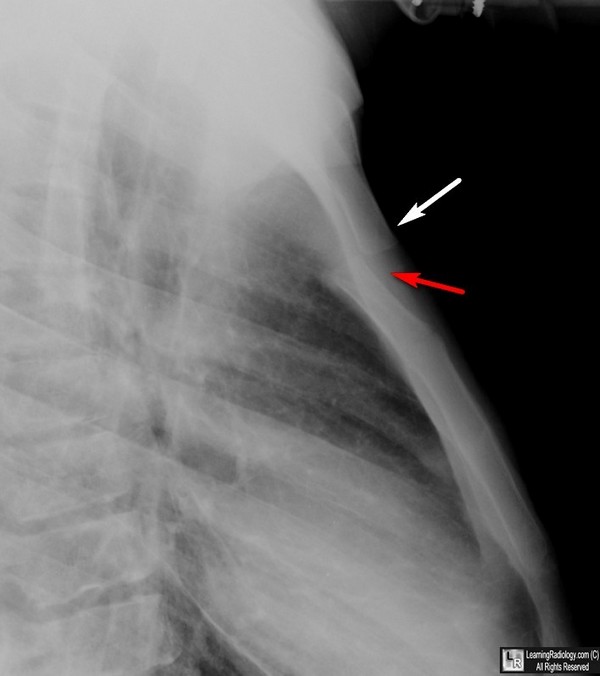

From www.learningradiology.com

LearningRadiology What Is A Mass On Your Sternum A doctor can diagnose the lump with imaging tests, and. Surgery is often necessary, and may. Causes of a lump on your chest can include a cyst, abscess, lipoma, or benign tumor. The chest wall plays an important role in keeping our organs safe. The chest wall is made up of the bones of the spine, ribs, and sternum, as. What Is A Mass On Your Sternum.